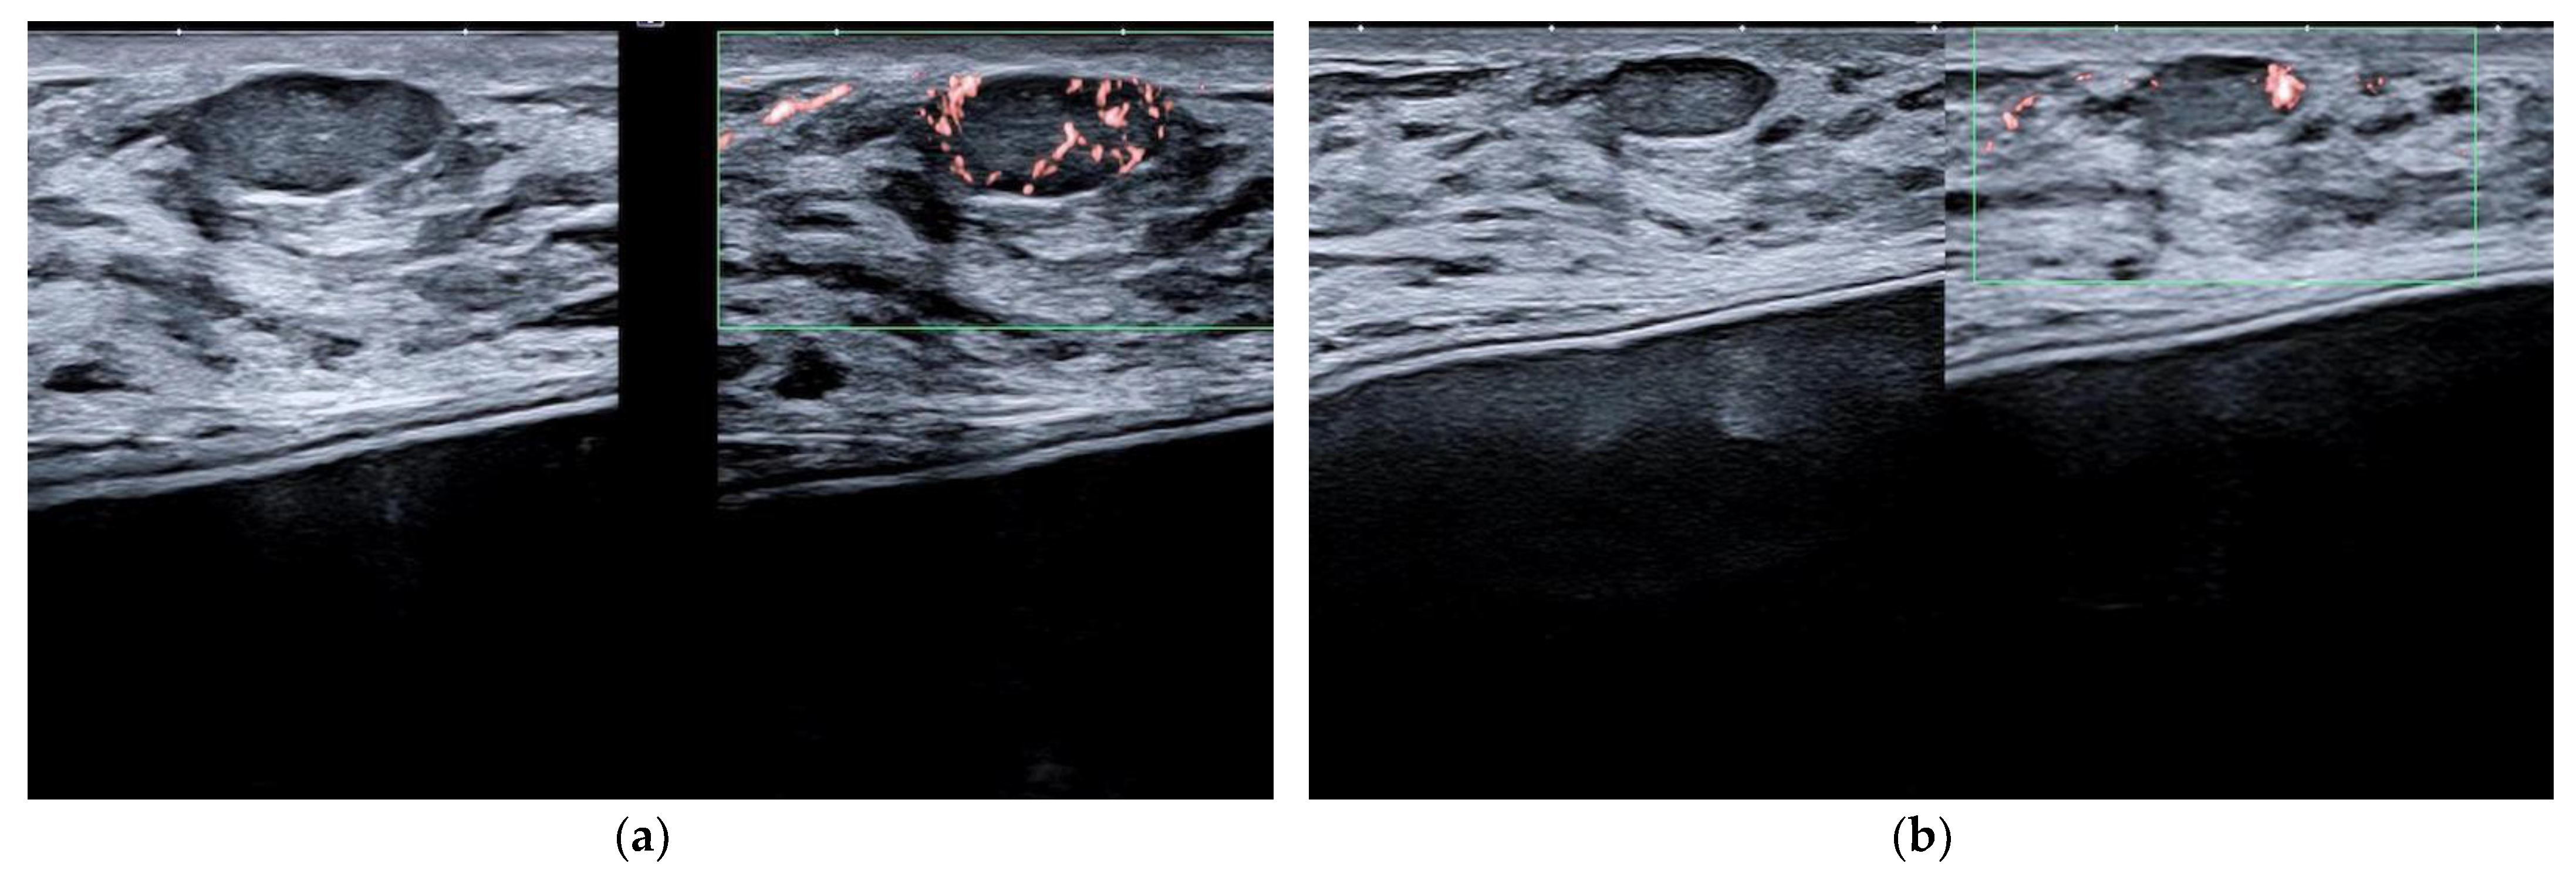

Figure 9. Fibroadenoma in a patient with a dual-plane breast implant. The quite superficial nodule is better depicted in its echotexture and vascularization by power-Doppler imaging when imaged at 22 MHz (a) than at 15 MHz (b).